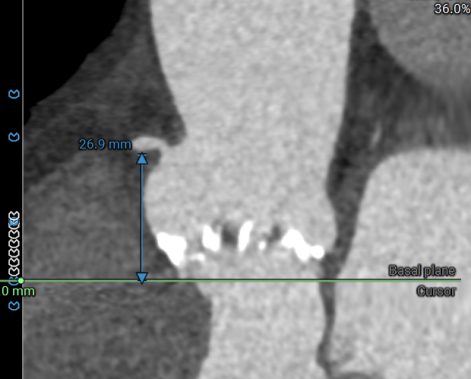

RIGHT CORONARY

右冠开口高26.9mm